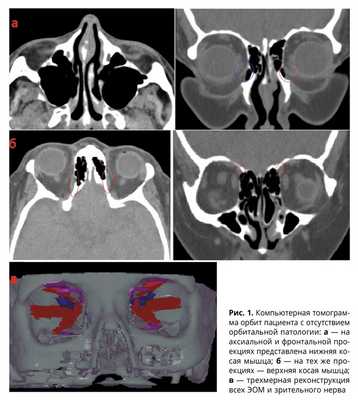

С целью изучения нормальных показателей костной орбиты, ее вершины изучены компьютерные томограммы 210 человек (266 орбит). У 56 пациентов с отсутствием орбитальной патологии были изучены обе орбиты (112 орбит). У 154 пациентов с односторонним поражением орбиты для определения показателей нормы была исследована интактная орбита (154 орбиты). Среди них 86 мужчин и 124 женщины. Средний возраст обследованных составил 41,2±10,4 лет.

Компьютерную томографию выполняли по стандартной методике с получением аксиальных и фронтальных срезов. Толщина срезов составляла 1,0 мм, шаг — 1,0 мм.

При расчете объема ЭОМ глаза и леватора верхнего века по отдельности (исключение составила нижняя косая мышца — ее объем вычисляли вместе с нижней прямой) оказалось, что наименьший объем имеют наружная и верхняя прямые мышцы. Наиболее крупными мышцами орбиты являются нижняя и внутренняя прямые, а также леватор верхнего века (рис. 1, табл. 2). Возможно, данным обстоятельством можно объяснить более частое первоначальное выявление изменений в нижней и внутренней прямых мышцах при некоторых заболеваниях орбиты (например — эндокринная офтальмопатия). Есть основание предположить, что при равных условиях увеличение первоначального объема ЭОМ на определенную величину приводит к более значительному увеличению и соответственно лучшей визуализации изначально больших по объему мышц.